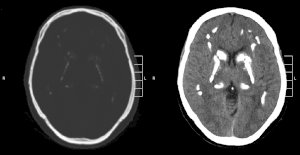

| CT scan of characteristic calcifications of the disease | |

Primary familial brain calcification[1] (PFBC), also known as familial idiopathic basal ganglia calcification (FIBGC) and Fahr's disease,[1] is a rare,[2] genetically dominant, inherited neurological disorder characterized by abnormal deposits of calcium in areas of the brain that control movement. Through the use of CT scans, calcifications are seen primarily in the basal ganglia and in other areas such as the cerebral cortex.[3]

Brain CT scan is the preferred method of localizing and assessing the extent of cerebral calcifications.

The calcification is usually identified on CT scan but may be visible on plain films of the skull.